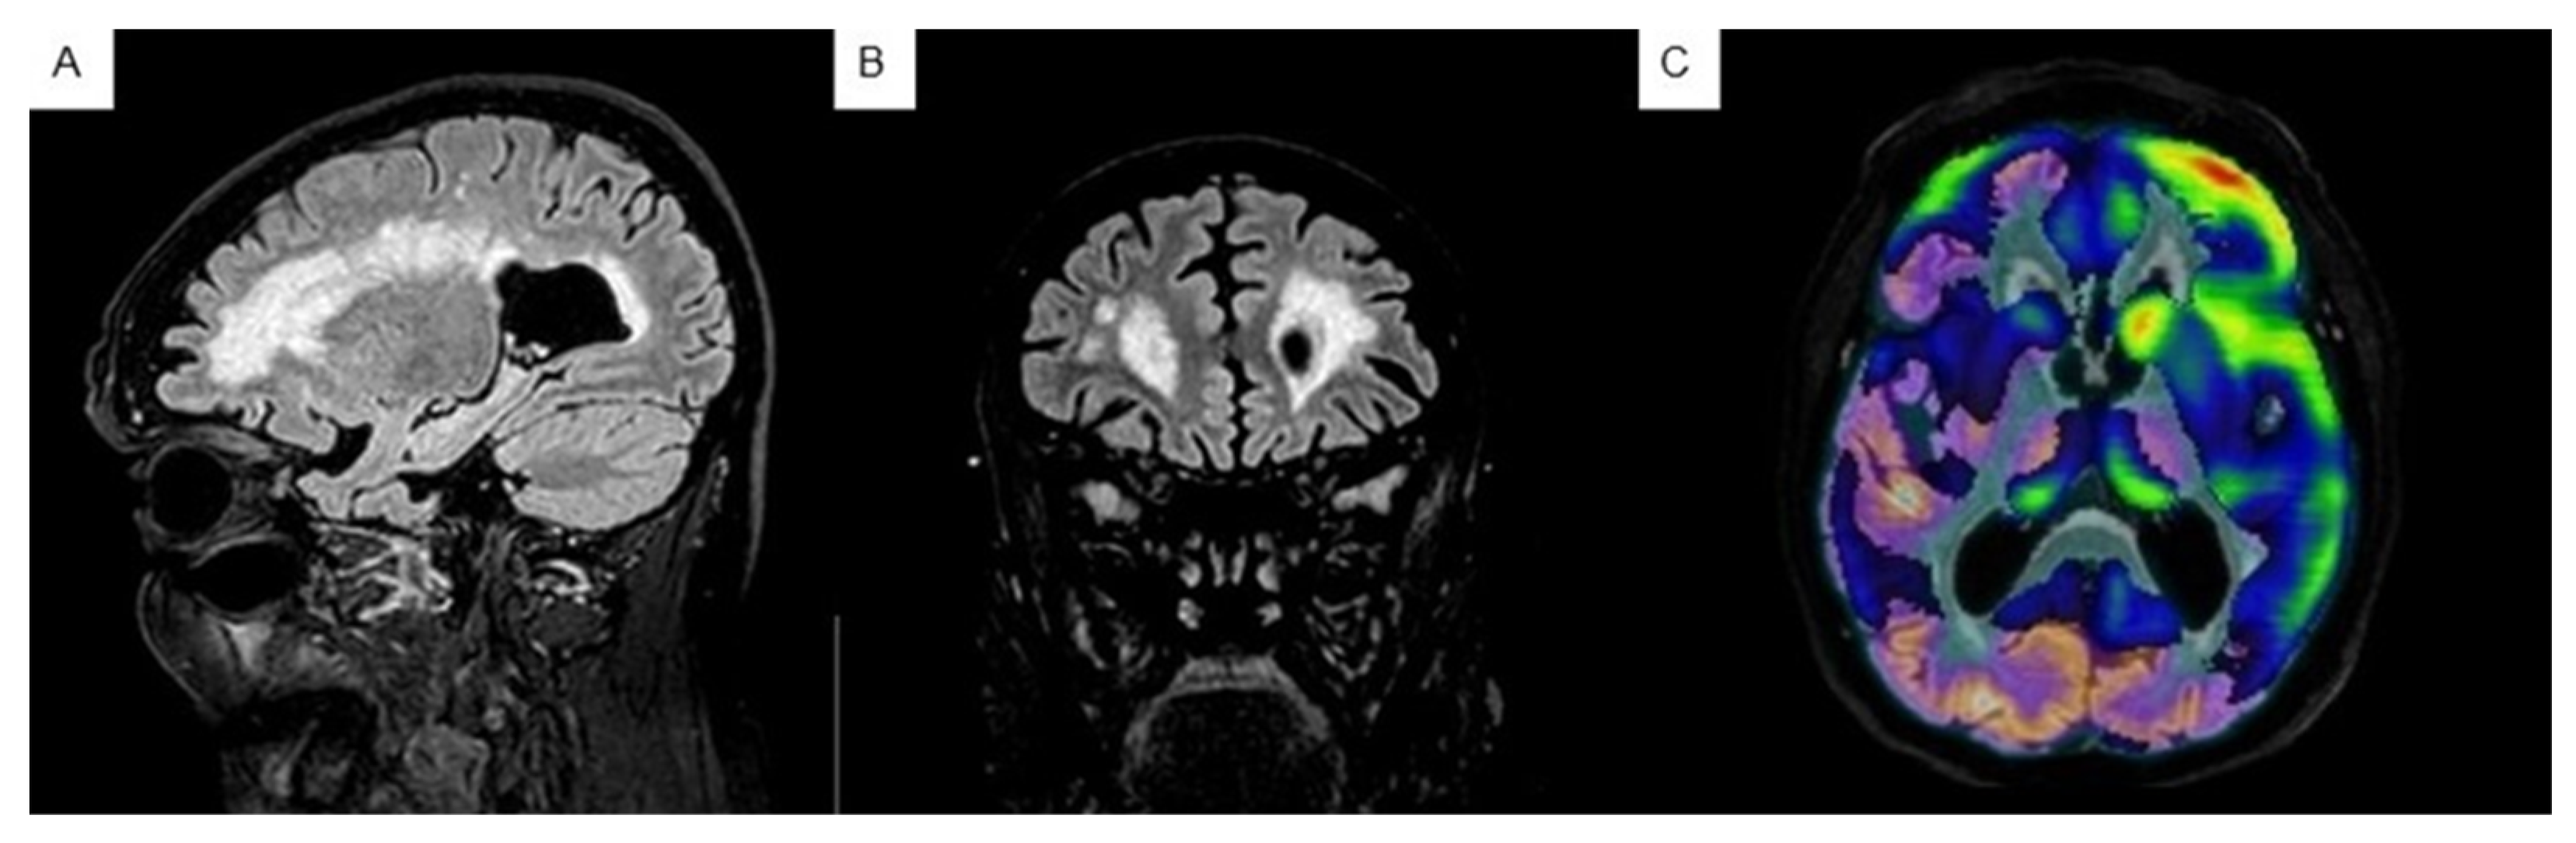

2.3.2. Neuroimaging Tests: